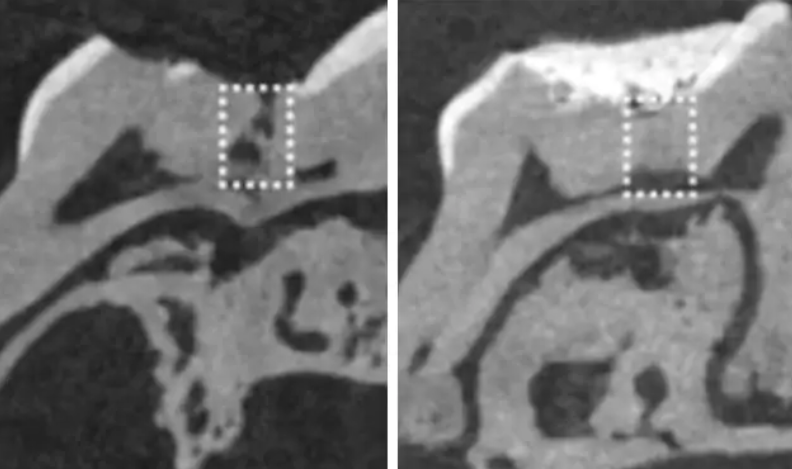

İlaç, kök hücreleri uyararak, dişlerin mezoderma kökenli kemiğe benzer yapıdaki temel katmanı olan 'dentin'in yeniden oluşumunu tetikliyor.

Dişler, aslında herhangi bir dış yardım almadan doğal olarak dentini yeniden üretebiliyor. Fakat diş özünün (pulpa), enfeksiyona (örneğin çürümeye) veya travmaya maruz kalarak, iç yapının üretimini başlatması gerekiyor. Ancak öyle olduğunda bile, dişin doğal olarak yeniden üretebildiği katman çok ince oluyor; yani genellikle derin olan çürüme kaynaklı oyukları onarmaya yetmiyor.

Habere göre 2017'de yapılan çalışmada, Tideglub ilacı emdirilmiş kollajenden yapılma biyo-çözünebilir minik süngerler, diş oyuklarına yerleştirildi. Süngerciklerin dentin oluşumunu tetiklediği görüldü ve 6 hafta içinde hasar onarıldı.